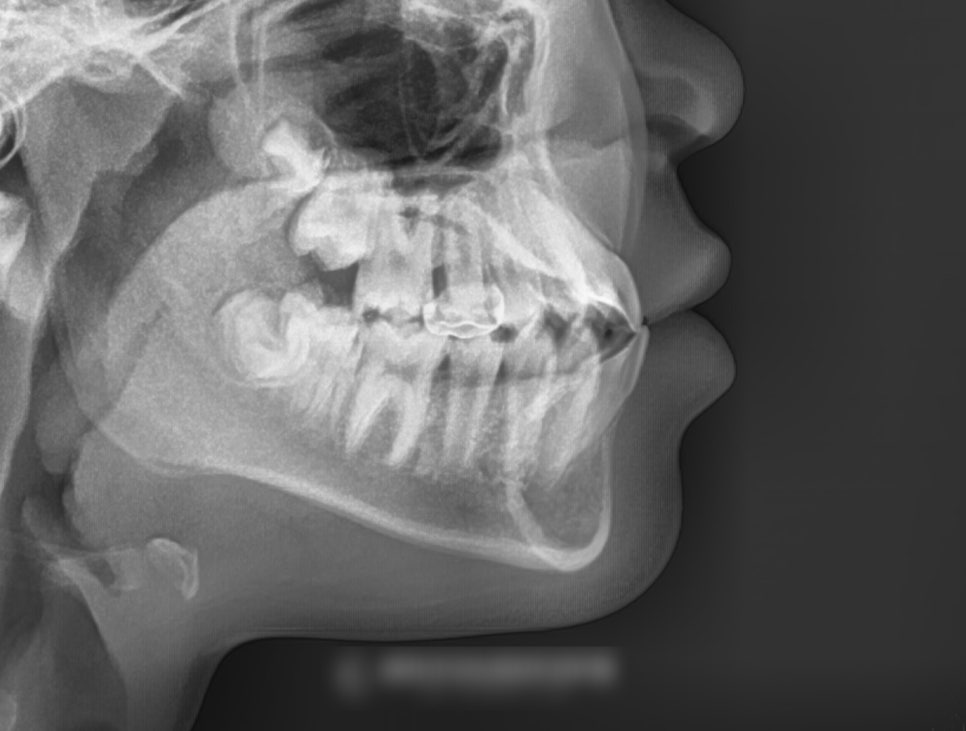

특히 이렇게 아직 성장을 진행 중인

어린이의 경우라면 더더욱 조기에

문제를 바로잡는 것이 중요합니다.

여러 검사를 통해

위아래 위치 관계 및 영구치 맹출 여부를 판단 후

주걱턱 치아교정 치료가 이뤄지는 게 좋습니다.